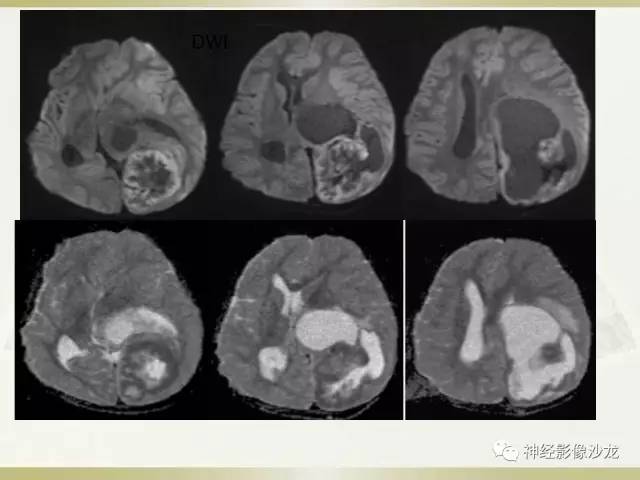

室管膜瘤?但DWI有点高

周老师说过两大特点,钙化,囊变,白老师说DWI高

其内有钙化,DWI高信号

应该提示恶性啊

@神经义工周刚-黄冈市医影像科 pnet还是实性多,幕上室管膜瘤囊性为主,在侧脑室周围。dwi高可能提示间变